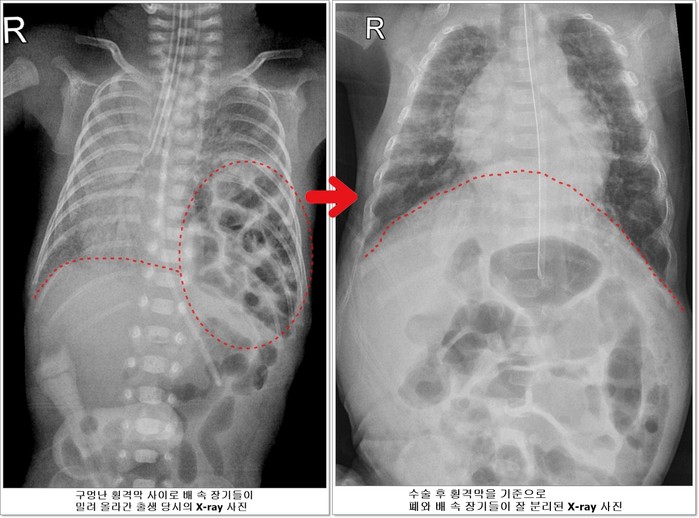

선천성 횡격막 탈장증이란 가슴 안의 심장과 폐를 배 속의 소화기 장기들로부터 분리해주는 횡격막에 선천적으로 구멍이 나는 질환이다. 배 속의 장기가 횡격막의 구멍을 통해 밀려 올라와 가슴안의 심장과 폐를 압박해 폐가 제대로 펴지지 않아 호흡곤란이 오고 심장기능 또한 떨어지게 된다.

| ▲전호삼 아기의 치료 전 후 X-ray사진 비교 |

하지만 호삼이는 이 모든 과정을 다 이겨내고 태어난 지 40일이 되던 5월 20일에 체중 1530g이 되어 소아외과 남궁정만 교수가 구멍 난 횡격막을 막는 수술을 성공적으로 시행했다.